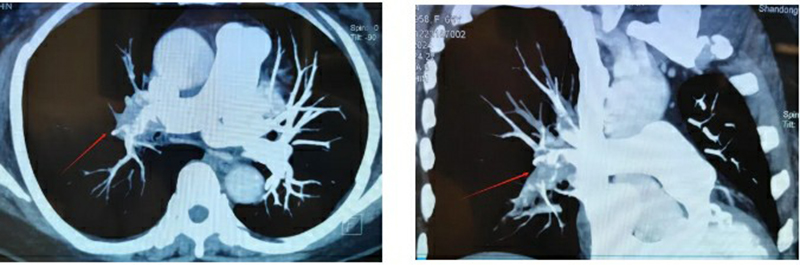

經(jīng)過初步檢查,叢樹賢副主任醫(yī)師發(fā)現(xiàn)孫大姨的情況十分危急,高度懷疑可能突發(fā)胸痛的原因與肺動脈栓塞有關(guān)。他當(dāng)機(jī)立斷,立即安排人員護(hù)送患者行肺部CTA檢查,結(jié)果令人震驚:孫大姨是雙側(cè)肺動脈及分支多發(fā)栓塞,其中右肺大面積栓塞,一旦栓子脫落,隨時(shí)有生命危險(xiǎn),十萬火急,必須馬上進(jìn)行搶救!立即啟動院內(nèi)VTE救治快速反應(yīng)機(jī)制,協(xié)調(diào)檢驗(yàn)科、放射介入科、心胸外科、護(hù)理部等多部門聯(lián)動,全力救治!